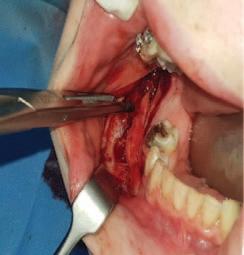

A sagittal split osteotomy approach for removal of a large cementoblastoma at the mandibular angle M. Cotter, Z.G. Khattak, C. Cotter 36